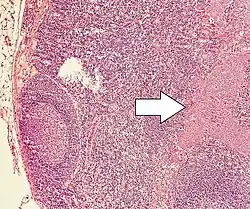

| Micrograph of a neuroendocrine tumor. H&E stain. | |